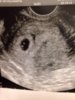

tuijottelen tätä. Vaikkakin on hyvin alussa, pieni papu jos senkään kokoinen vielä niin taisin säikkyä tänään aamulla ihan turhia.. Eiköhän tuo oo yhtä sitkeä kun äitinsä! Tänään on tullu huonon olon ohessa siivoiltua ja nyt teen lasagnea! Oon vähän yksinäinen, niin ehkä mua helpottaa et pääsen tänne teidän seuraan.. :)